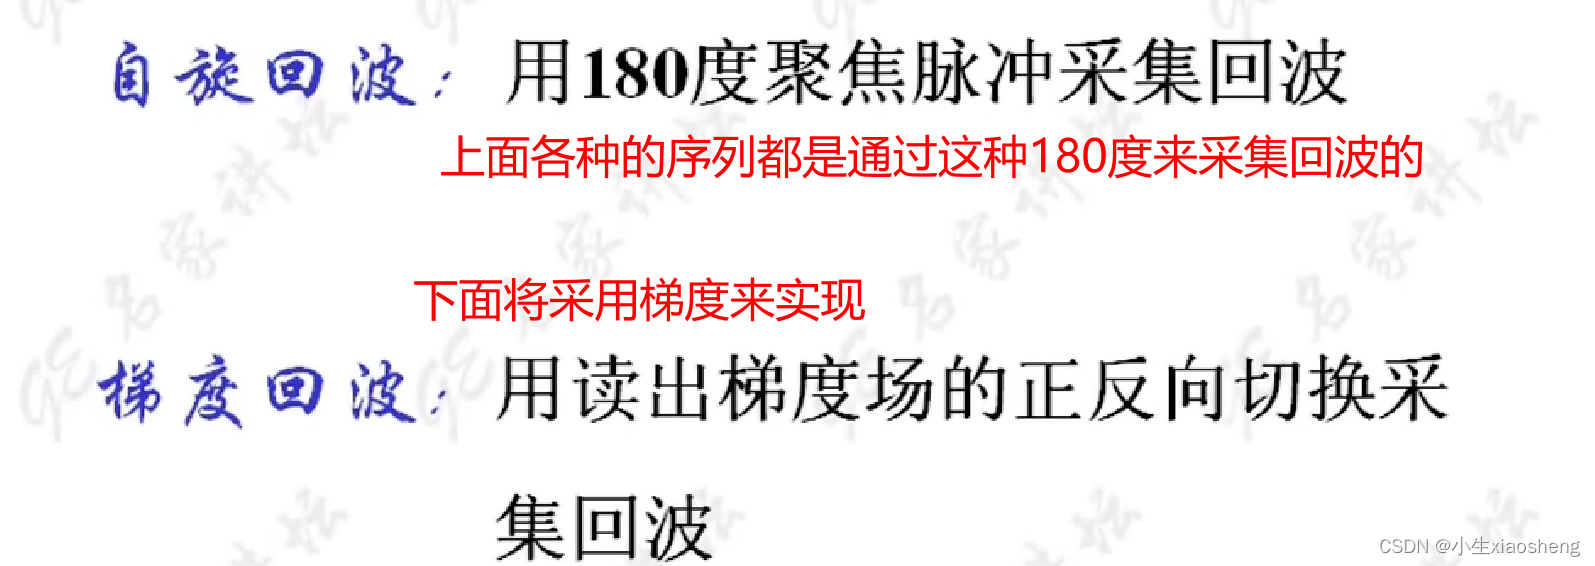

自旋回波--90度和180度填充K空间;反转恢复--在自旋的基础上两边加180度;梯度回波--消除每次脉冲留下的影响,以及波的次数;propeller==》K空间填充技术和FSE或FIR结合用于减少运行伪影;EPI==》采集方式,一次激发采集多个回波的形式但与单次不一样;PRESTO和GRASE==》前面几种的一种结合形成新的。

三、自旋回波类序列

五、梯度回波类序列